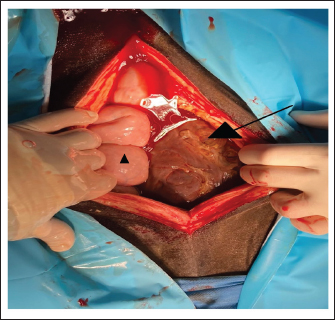

A 7-year-old warmblood mare was referred to the Department for Horses, University of Leipzig, because of a suspected impaction of the ascending large colon. On initial examination, the mare showed tachycardia (60 beats/minute), tachypnea (40 breaths/minute), and fever (38.7°C). She had pale mucous membranes and a prolonged capillary refill time of more than 3 seconds. Borborygmi were decreased and she showed mild to moderate abdominal discomfort. A routine ultrasonographic examination of the abdomen revealed a large amount of echogenic, swirling free fluid suggestive of hemoperitoneum (Fig. 1). Free fluid was visible inguinal bilaterally and ventrally and hemoperitoneum was confirmed by abdominocentesis. The abdominal fluid was red, turbid, and contained mostly erythrocytes (5.73 T/l). Transrectal palpation revealed a firm structure in the ventral abdominal cavity, which extended across the abdomen from the right to the left side. This structure was initially suspected to be an impaction. Nasogastric intubation yielded no reflux.

Fig. 1. Ultrasound examination of the abdomen on the first admission. The image was taken at the left inguinal region. Hemoperitoneum was suspected based on a large amount of echogenic and swirling free fluid (*) and was confirmed by abdominocentesis. The honeycomb structure (triangle) was visible in the entire ventral side of the abdomen, pushing against the spleen and stomach on the left side and reaching the kidney and liver on the right side. The honeycomb structure was visible up to the 9th intercostal space.